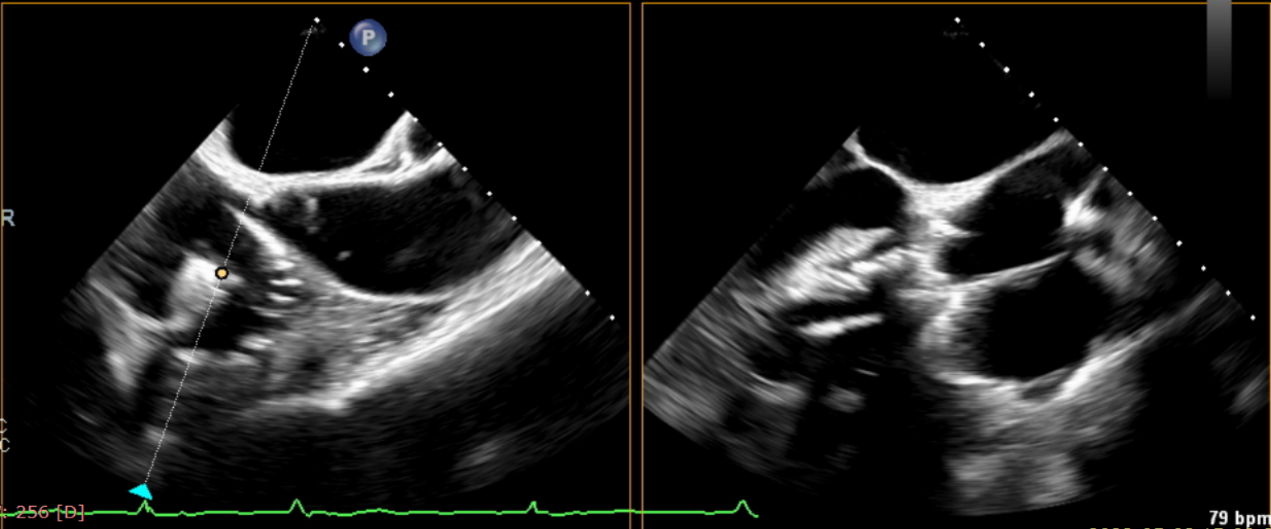

術后超聲提示無瓣周漏

術后超聲提示僅殘余輕微瓣周漏